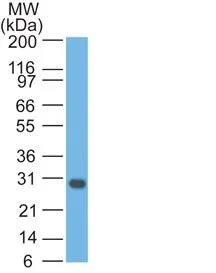

- Description: Bcl-x belongs to the Bcl-2 family of proteins and plays a crucial role in apoptosis. Bcl-X has two isoforms: Bcl-XL (long), a 26 kDa protein which suppresses cell death, and Bcl-XS (short), a 178 amino acid protein lacking a 63 amino acid domain which functions as a dominant inhibitor of Bcl-2 and promotes apoptosis. This MAb reacts with both Bcl-XS and Bcl-XL proteins, and shows no cross-reaction with Bcl-2 or Bax proteins._x000D__x000D_Primary antibodies are available purified, or with a selection of fluorescent CF® Dyes and other labels. CF® Dyes offer exceptional brightness and photostability. Note: Conjugates of blue fluorescent dyes like CF®405S and CF®405M are not recommended for detecting low abundance targets, because blue dyes have lower fluorescence and can give higher non-specific background than other dye colors._x000D_ _x000D_

- Applications: IHC, FFPE (verified) | WB (verified)

- Validated Applications: IHC, FFPE, WB

- Molecular Weight: 27 kDa

- Additionnal Information: Higher concentration may be required for direct detection using primary antibody conjugates than for indirect detection with secondary antibody|Immunofluorescence: 0.5-1 ug/mL|Immunohistology formalin-fixed 0.5-1 ug/mL|Staining of formalin-fixed tissues requires boiling tissue sections in 10 mM Tris with 1 mM EDTA, pH 9.0, for 10-20 min followed by cooling at RT for 20 minutes|Flow Cytometry 0.5-1 ug/million cells/0.1 mL|Western blotting 0.5-1 ug/mL|Optimal dilution for a specific application should be determined by user